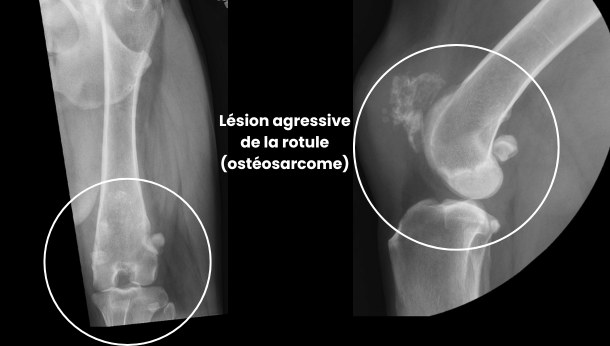

Les examens d’imagerie radiographique ont révélé :

• une lésion ostéolytique et ostéoproliférative localisée à la rotule

• des remaniements compatibles avec un processus tumoral agressif, confirmé par biopsie